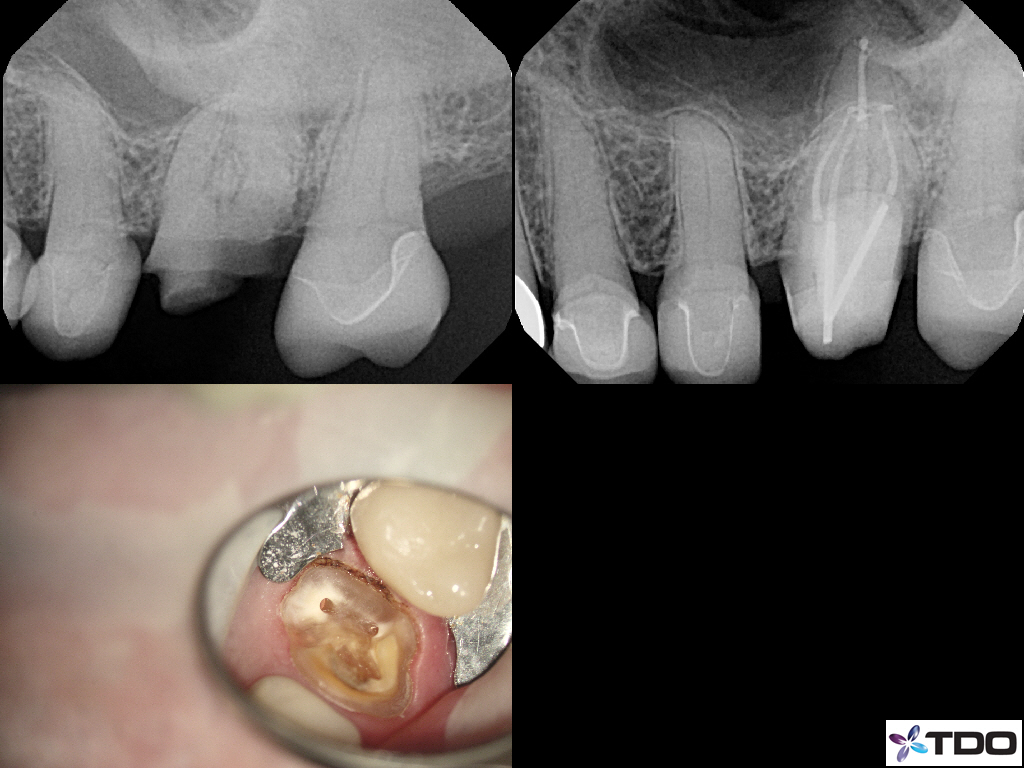

These cases show a level of commitment to conservative endodontics rarely seen in endo today. Plus the restorative excellence is inspiring and should stimulate all endodontists to up their game and help others realize how important the restorative aspect of endodontics is.